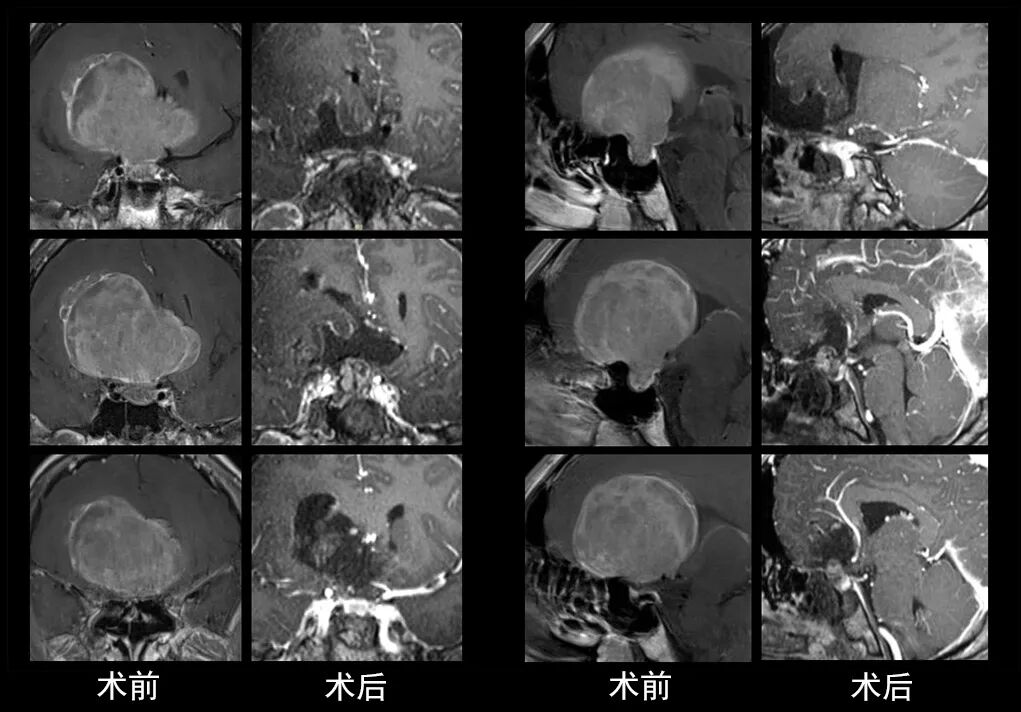

本研究中采用联合手术策略的代表性病例展示:

左右滑动查看更多

图片

case 3

case 4